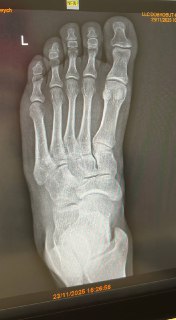

Став лайк, якщо в тебе рентгенівські суглобові щілини нормальної ширини👍

Все гуд, перелому немає. Звʼязки😌